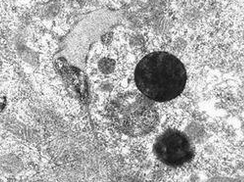

脉络膜骨瘤(choroidal osteoma)是由成熟骨组织构成的、位于脉络膜一种良性肿瘤。1978年由Gass等正式命名。脉络膜骨瘤是由成熟骨组织构成的位于脉络膜一种良性肿瘤。1978年由Gass等正式命名。肿瘤多位于近视盘附近,呈黄白色或桔红色的扁平隆起,可见色素沉着,肿物边缘不规则,似伪足向四周伸出,可形成视网膜下新生血管膜,伴有出血或浆液性视网膜脱离。脉络膜骨瘤多见于20~30岁的健康女性,因肿瘤生长及视力变化缓慢,所以临床就诊年...